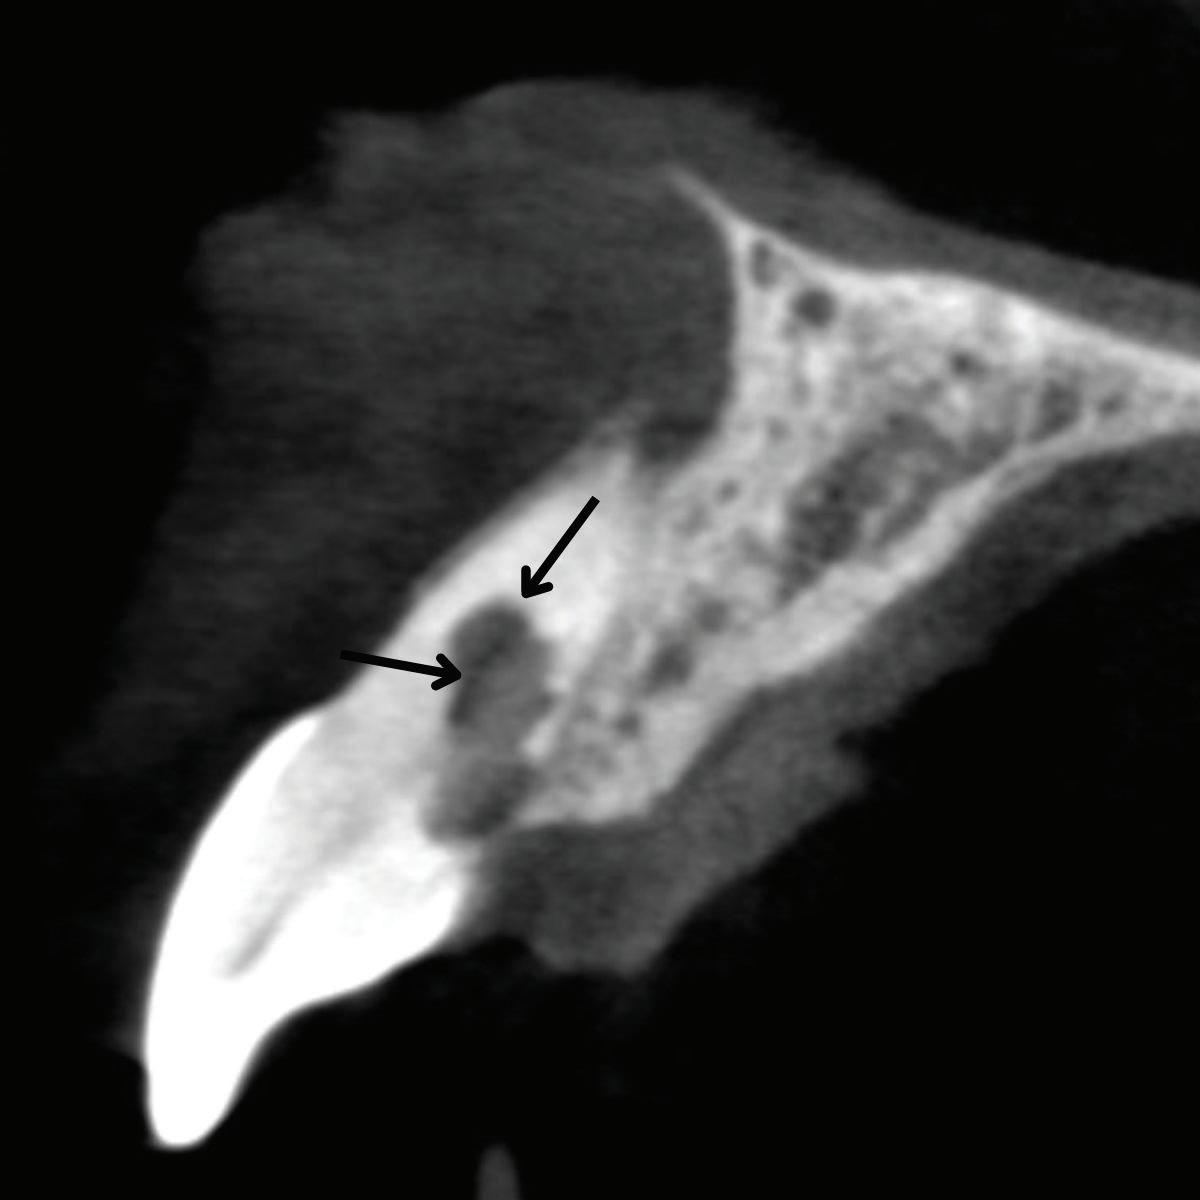

When endodontic irrigants or materials are extruded in teeth with fenestrations, they not only exit beyond the apex but also may enter directly into soft tissue or mucosal spaces, dramatically increasing the risk of postoperative swelling, pain, and delayed healing. In a recent retrospective case series investigating sodium hypochlorite extrusion injuries, fenestrations were identified in all 26 reported cases (Fig 3).23

Fig 3. Sodium hypochlorite was extruded through a perforation that occurred during endodontic treatment of the maxillary left canine, causing immediate bruising, swelling, and pain.

Fig 4. Fenestration involving the maxillary right first molar. A. The periapical radiograph fails to demonstrate the presence of a fenestration at the mesiobuccal root. B. The axial CBCT image clearly depicts the fenestration. C. The coronal CBCT image also reveals the fenestration.

It also could be argued that the potential for iatrogenic complications, including extrusion-related nerve injuries or sinus involvement, supports a more universal application of preoperative CBCT, especially in posterior teeth or anatomically high-risk zones. For instance, bony fenestrations, which create direct communication between the root surface and soft tissue due to absence of cortical bone, are virtually invisible on standard 2D radiographs. These defects significantly increase the risk of overinstrumentation; endodontic irrigant and obturation material extrusion; and postoperative inflammation, particularly when the root apex lies adjacent to neurovascular structures or sinus cavities. CBCT is the only reliable tool to detect fenestrations preoperatively. It allows visualization of cortical bone thickness and can identify discontinuities in the buccal or lingual plate that predispose to soft tissue perforation (Fig 5).

In a CBCT-based study by Nalbantoğlu et al, fenestrations were identified in approximately 35.7% of maxillary anterior teeth, with the majority occurring in the apical third of the root. 28 Dehiscence was observed in 20% of teeth, and a significant proportion of cases were associated with thin buccal bone, particularly in patients with periodontal biotypes exhibiting bone thickness of 1 mm or less. These findings highlight the vulnerability of anterior teeth, especially in individuals with thin cortical bone, to structural defects such as fenestrations.

Fig 5. Fenestration involving the maxillary left central incisor. A. The periapical radiograph fails to demonstrate the apex protruding into the sinus. B. The CBCT 3D reconstructed volume clearly demonstrates the fenestration.